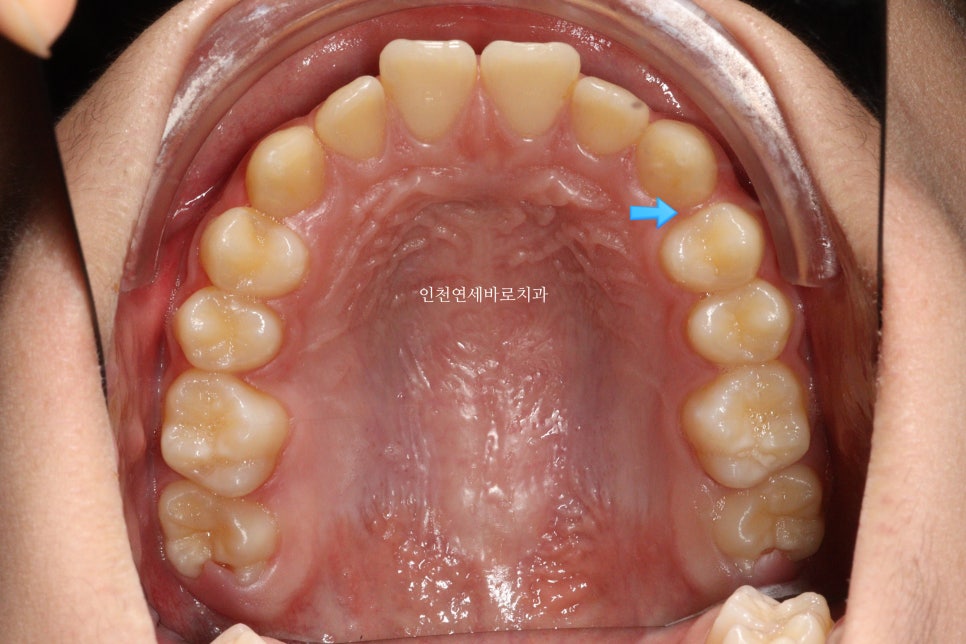

이 아이는 앞니 두개가 튀어나온 것을 고치고 싶어했습니다.

치료 전과 후 입니다.

앞니가 후방이동 한것이 확인됩니다.

우리는 부분교정을 한것이 아니라 간단한 전체교정을 한것입니다.